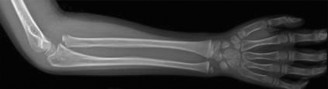

Distal Radius Greenstick

- Radiographic Findings: AP and lateral radiographs of the left wrist demonstrated a transverse greenstick fracture of the distal metaphysis of the radius, approximately 2 cm proximal to the physis. The fracture involved the dorsal cortex, with an intact volar cortex, resulting in approximately 10 degrees of apex volar angulation. There was no significant displacement or rotational deformity. The distal ulna and its physis were unremarkable.

- Classification: Greenstick fracture of the distal radius.

Distal Radius Greenstick Fracture

- Decision: Non-operative management with closed reduction and casting.

- Rationale: Greenstick fractures, by definition, involve an intact cortex, which often provides inherent stability. The apex volar angulation of 10 degrees is well within acceptable limits for a 7-year-old distal radius fracture, which has excellent remodeling potential. Surgical intervention is rarely indicated unless angulation exceeds acceptable thresholds (typically 20-25 degrees in this age group, depending on skeletal maturity) or if there is significant rotational deformity.